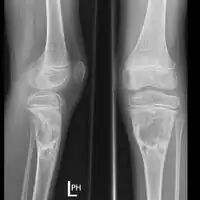

| Aneurysmal bone cyst (fibula, around knee). | |

X-ray and CT scan show lytic expansion lesions with clear borders.[1] Expansion of cortex gives the lesion a balloon-like appearance. Larger lesions may appear septated.[10] MRI reveals fluid levels.[1] Bone scan shows outer radiotracer uptake, with a central dark area.[1]

X-ray: ABC large long bone of lower leg near knee